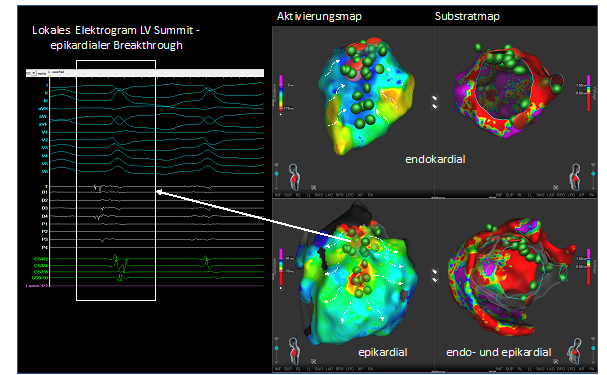

Hochauflösendes, dreidimensionales Aktivierungs- und Substratmap des linken Ventrikels.

Abb. 1: Hochauflösendes, dreidimensionales Aktivierungs- und Substratmap des linken Ventrikels. Nachweis eines fraktionierten Elektrograms an der epikardialen Durchbruchstelle der VT im Aktivierungsmap. In Grün sind die PFA-Applikationen, in Rot die Hochfrequenzstrom-Applikationen zu sehen.

Trotz der durchgeführten Ablation entwickelte die Patientin am Folgetag einen elektrischen Sturm, manifestiert durch zahlreiche ICD-Therapien, einschließlich 30 antitachykarder Überstimulationen und 9 ICD-Schockabgaben. Unter intravenöser Amiodaron- und Lidocaintherapie verlangsamte sich die Zykluslänge und es persistierte eine anhaltende „Slow-VT“ mit einer Herzfrequenz von 110-120/min (EKG der VT-Hauptmorphe: II, III, aVF positiv, I negativ, Pattern-Break V1-V2, V3-V6 positiv). Bei einer linksventrikulären Ejektionsfraktion von 20%, wurde die Slow-VT hämodynamisch nur noch grenzwertig von der Patientin toleriert. Es wurde die Indikation zur erneuten VT-Ablation, nun mit epikardialem Zugang, gestellt. Nach Erstellen eines dreidimensionalen endo- sowie epikardialen Aktivierungs- und Voltagemaps mit einem Lattice-Tip Mapping-/ und Ablationskatheter zeigte sich eine ventrikuläre Tachykardie, welche von endokardial aus der Region des linksventrikulären (LV)-Summit nach epikardial durchbricht. Nach Darstellung der Koronararterien erfolgte zunächst die Gabe von Nitroglycerin intravenös und die Ablation mit Pulsed-Field-Ablation (PFA) im epikardialen Bereich des LV-Summit. Bei fehlender Terminierung erfolgte der Wechsel nach endokardial und die Ablation vis-a-vis mit Radiofrequenz (RF) und sofortiger Terminierung der VT. Im Anschluss erfolgte eine Konsolidierung des Bereichs mit PFA und RF-Läsionen. Es war auch nach Wartezeit keine weitere VT mehr induzierbar. Es kam zu keinerlei Komplikationen. Auch einen Monat nach der Prozedur zeigte sich ein anhaltender Sinusrhythmus ohne weitere ventrikuläre Arrhythmie-Episoden.